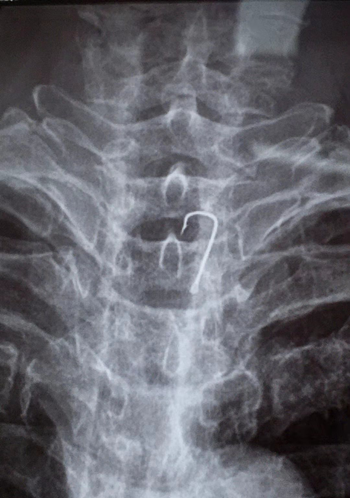

【点赞】八旬老人误吞鱼钩半月,王德乐医生展“绣花”功夫助脱险!

近日,一名84岁的老大爷在家吃鱼后出现胸部疼痛,当时没有重视,疼痛症状持续了半个多月才到我院眼耳鼻咽喉科求医,接诊医生为老大爷做X线影像检查时发现食管胸段滞留一枚鱼钩据了解鱼钩滞留在食管内时间长达半个月,很可能已引起食管溃疡甚至穿孔,并且锋利的鱼钩距离主动脉弓很近随时可能划破毗邻大血管引起致命性出血情况紧急,必须立即设法取出

众所周知,鱼钩前端都有一个锋利的倒刺,而这种倒刺插入食管黏膜后,强行入口拔除存在很大风险和不确定性,严重时有转胸外科手术取出的可能。耳鼻喉科主任王德乐接到首诊医师反馈者病情后马上并组织团队讨论,决定开通绿色通道,急送手术室为患者施行全麻下食管镜探查+异物取出术。

麻醉科团队的配合下,王德乐凭借丰富的临床经验

“绣花”功夫经食管镜将于胸段食管壁的鱼钩反向顺利取出鱼钩的尖端插入食管黏膜长达1cm,避免了转胸外科开胸取鱼钩的风险!患者经治疗后,康复出院!